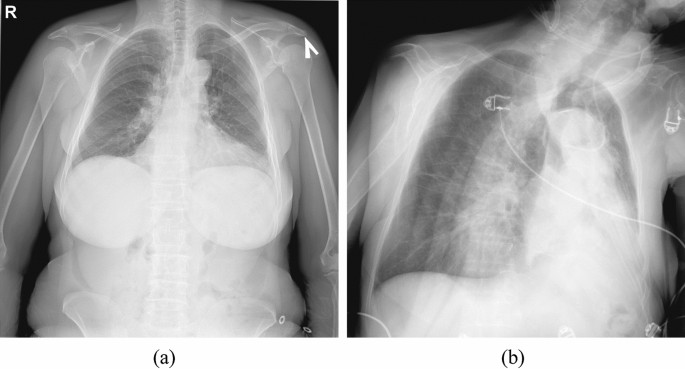

A physician has visually reviewed cases with the framework results. This Figure presents some potentially challenging examples of chest X-rays labeled as abnormal by the framework with the corresponding abnormality heatmaps. (a) This case has been manually labeled as pathological requiring a CT image for specific abnormality confirmation. (b) An X-ray with no visual abnormalities. According to the physician’s opinion, the framework mis-labeled this X-ray as abnormal due to a wrong patient position so that his shoulder blades overlapped with the lung tissue. (c) The physician confirmed the presence of infiltration in the location marked by the framework. (d) The algorithm correctly labeled the X-ray by capturing fibrosis but did not highlight pleural effusion and broken ribs.

Before being analyzed for chest abnormalities, an input image passed through several preprocessing steps. First, a neural network scanned the image to recognize if it represents a conventional or grayscale-inverted X-ray. An X-ray marked as grayscale-inverted was then converted to conventional. Second, a neural network scanned the image to recognize if it represents a frontal chest X-ray or lateral chest X-ray, or some other image. An input not labeled as a frontal chest X-ray is marked as defected and no further analysis is performed on it. The EfficientNet classification network architecture was used for both preprocessing steps. The networks were trained with a combination of binary cross-entropy and focal losses, Adam optimizer, and l2 regularization with a weighting factor of 0.0001. In the third preprocessing step the approximate location of the lung fields was estimated. The X-ray was converted into an integral image to compute Haar, a histogram of oriented gradients (HoG), and local binary pattern features73. These features were matched to the lung field descriptors to find the approximate locations of the lung fields in the X-ray. The lung fields are cropped from the input X-ray using the bounding box with safety margins. The lung field detection was needed to normalize the location of the target anatomy, remove unnecessary parts of the head and abdomen that could be present in the X-ray, and recognize defective X-rays where lung fields are cropped. The preprocessing of the input image was needed to automatically recognize if it actually represents a frontal lung X-ray of acceptable quality. It was required by the experiment organizers for frameworks to recognize and report defective inputs. It was considered an error if an automated report is generated for a non-lung X-ray or marked as defective a lung X-ray (Fig. 3b). The cropped lung field region was then rescaled to 512 × 512 size and the intensities were normalized to the [0; 1] range.